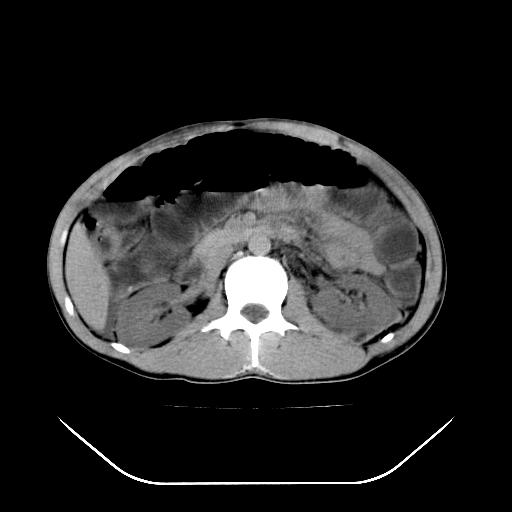

我不同意守望可西里老师所说的有输尿管的血液凝积一说,首先从这个图像来看输尿管的走行太偏外了,输尿管是肾盂向下延续的部分,开始在腰大肌的外缘,逐渐向内偏移,接近或越过腰椎横突的外端。而守望可可西里老师所指的这段图像位置太靠外了,且总是伴行在一段肠管的前缘。第二,如果有血液的凝积,可造成肾盂肾盏的扩张积水,而这个病人的肾盂肾盏的形态一直很好。

综上所述,考虑1:左肾挫伤并包膜下血肿2:少量腹腔积液3:肠梗阻的可能

除了1:左肾挫裂伤并肾周血肿;

2:少量腹水

第二次ct检查后:临床医生腹水穿刺后考虑肠系膜动脉破裂,后实行剖腹探查:于空肠距离十二指肠90cm处发现肠管破裂,破裂口较小;修补后关腹。

谢谢各位老师精彩的讨论